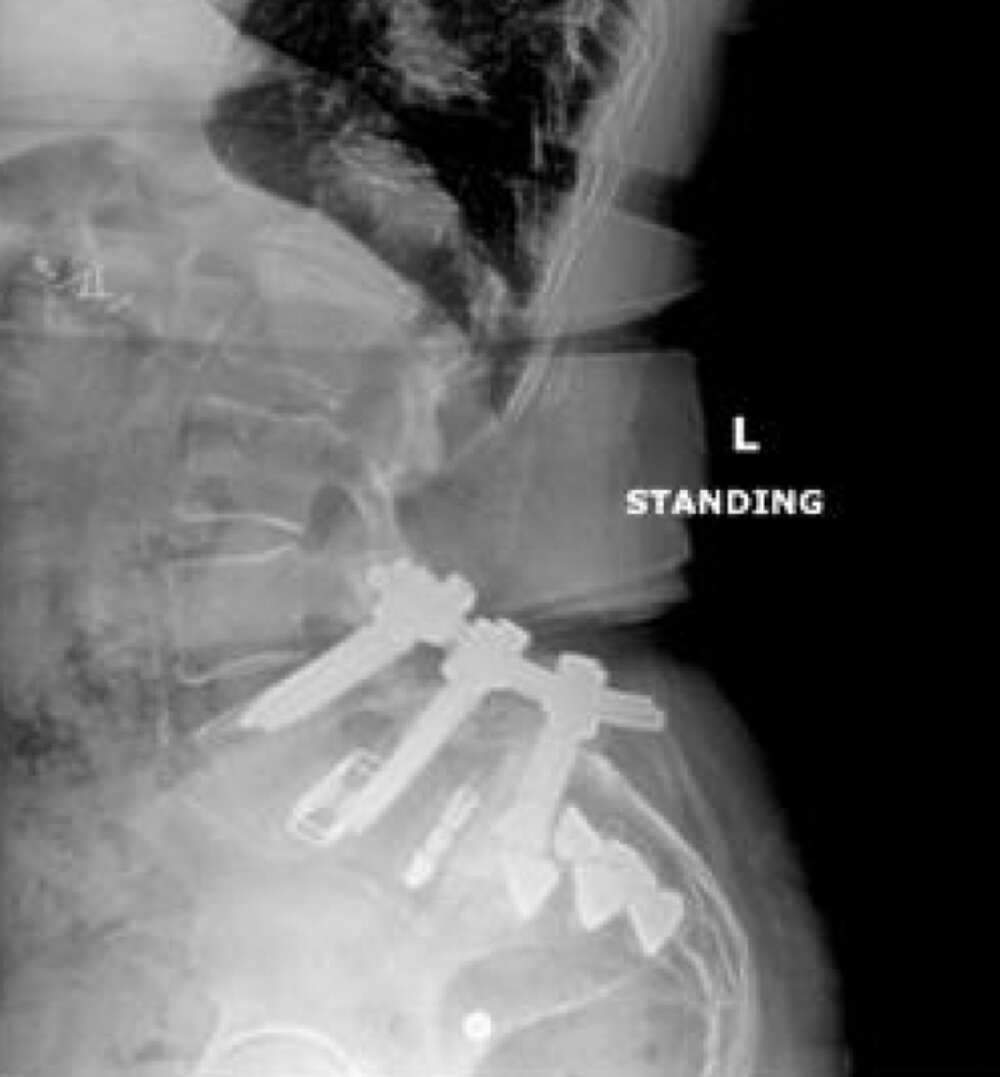

- High lumbar lordosis (77°) & pelvic incidence (86°)

- L4-5 & L5-S1 MIS transforaminal interbody fusion, November 2017

- Revision open L4-S1 fusion for pseudoarthrosis and hardware loosening, March 2019

- CT of lumbar spine at +2 years post-op shows confirmation of the SI joint fusion.

Inline dennis 04